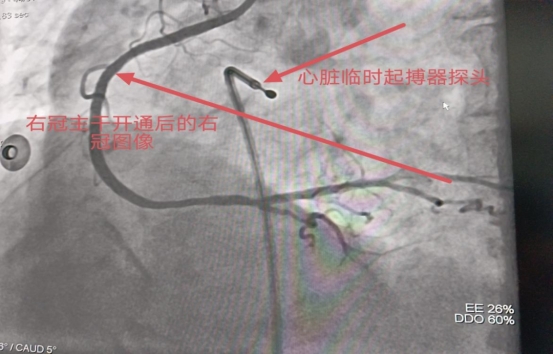

患者心功能极差、心房纤颤、心动过缓,处于心源性休克状态,需依靠升压药物维持血压,为保障介入手术顺利进行,刘仲伟教授决定立即行临时起搏器植入以防止心源性猝死的发生,起搏器植入后顺利在闭塞的右冠主干植入导丝,先行冠状动脉内血栓抽吸取栓及冠状动脉内溶栓术,再行球囊扩张后顺利开通右冠并植入支架,术后IVUS检查显示支架贴壁良好,血流恢复至TIMI3级,手术完美结束。术前心电图系急性ST段抬高型心肌梗死+心房纤颤,术后心房纤颤转复为窦性心律,ST段较前回落!上级教授精湛的冠脉介入技术带给了患者福音,术后患者胸痛症状即刻缓解,心房纤颤转复为窦性心律后血压逐渐恢复正常,转入监护病房进一步康复,本次救治过程充分体现了现代介入手术“及时、精准、微创、安全、高效”的显著优势。